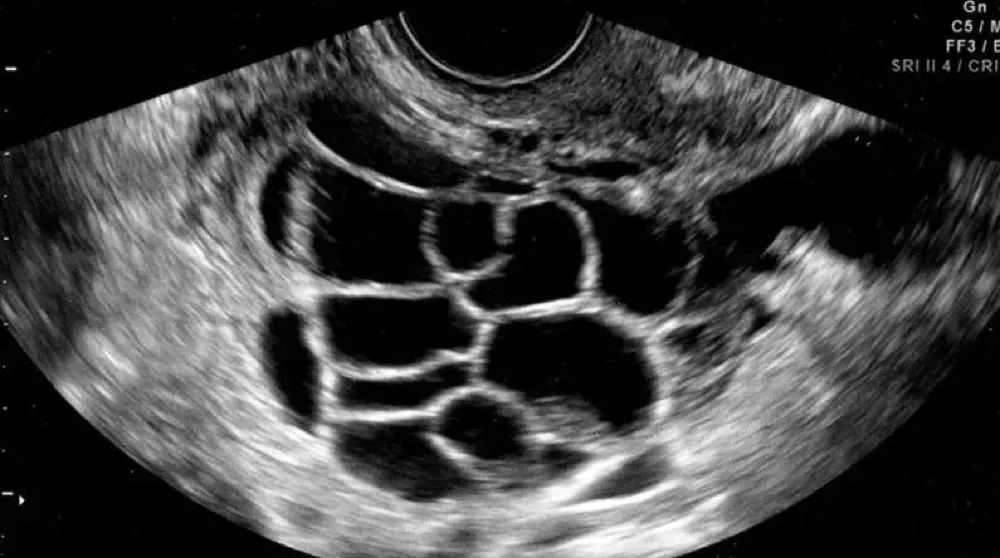

DRC indeterminada ou você esqueceu de fazer o básico? Veja tudo aqui

DRC “indeterminada” raramente é falta de diagnóstico — quase sempre é falta de método. Tempo de evolução, urina bem avaliada, USG renal e história clínica dirigida mudam conduta e evitam erros comuns na prática nefrológica.